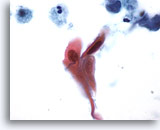

Figure 76

Sputum

Orangeophilic cells with hyperchromatic nuclei are suspicious for squamous cell carcinoma. 60x

Sputum

Orangeophilic cells with hyperchromatic nuclei are suspicious for squamous cell carcinoma. 60x

Figure 76

Sputum

Orangeophilic cells with hyperchromatic nuclei are suspicious for squamous cell carcinoma.

60x

Sputum

Orangeophilic cells with hyperchromatic nuclei are suspicious for squamous cell carcinoma.

60x